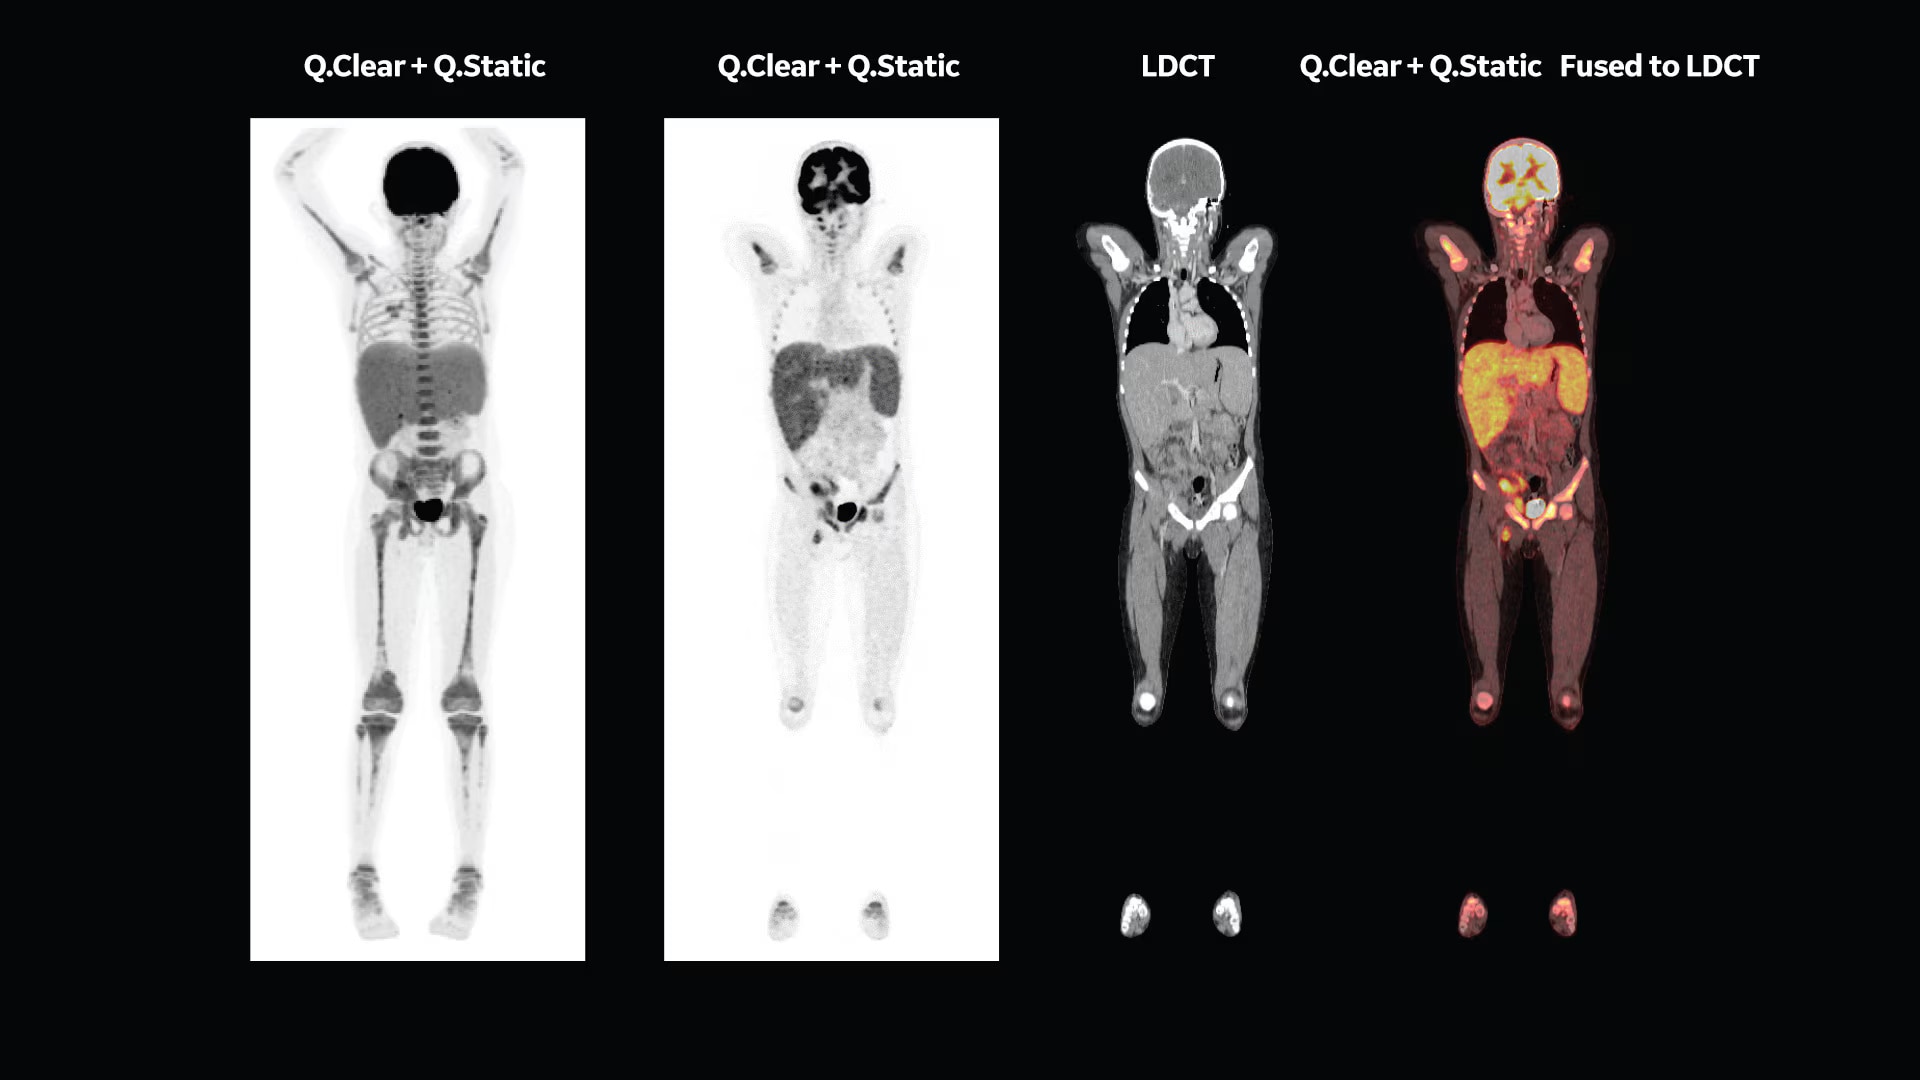

Q.Clear (BSREM): accurate data points to trusted treatment

Since its introduction, Q.Clear has delivered fast and efficient quantitation readings for confident diagnosis and precise treatment response assessment. Up to a 2x improvement in quantitative SUV (SUVmean). Up to a 2x improvement in image quality (SNR).